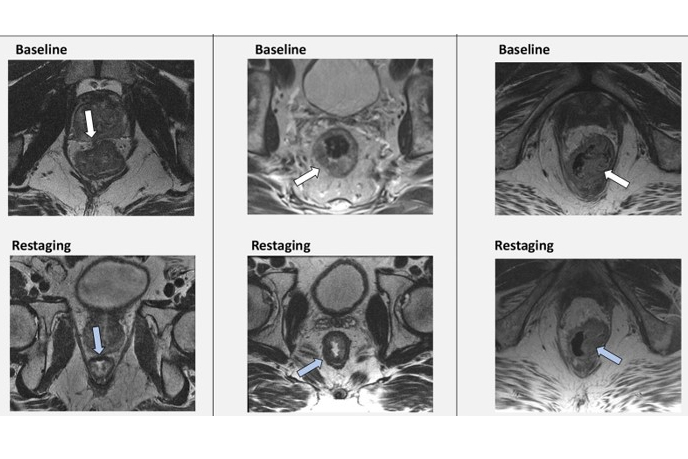

The researchers recruited 42 patients with histologically confirmed rectal cancer. After standard initial clinical staging with CT and/or MRI, all patients were scheduled for preoperative radiotherapy or radiochemotherapy. Before the treatment, all patients were restaged with whole-body, F-18 FDG-PET/MRI (Biograph mMR, Siemens Healthineers).

In addition, in 11 cases, PET/MRI led to an upstage; in 16 cases, it resulted in a downstage; and in 15 cases, the clinical stage remained unchanged, the researchers reported.

“Our results show that PET/MR changed the clinical stage in 64% of the patients and altered clinical management in 26%, confirming that PET/MRI is functional in restaging [rectal cancer] patients,” the group wrote.